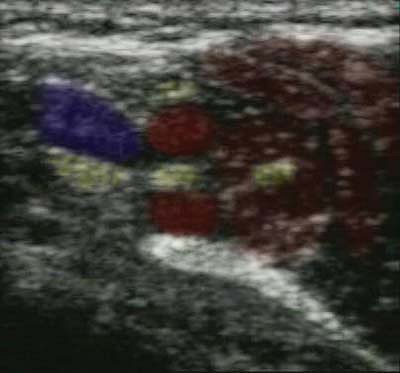

nature. Veins can be distinguished by their compressibility. Pressing

to collapse. Color flow Doppler imaging can also be used to identify

and distinguish arteries and veins. By convention, blood flowing toward

the probe is colored red. Blood flowing away from the probe is colored

blue. Blood flowing perpendicular to the probe remains black. Velocity

gates can be set to measure the flow velocity. High velocities are

usually arteries. Low velocities are usually veins.

on ultrasound. Bones are hyperechoic and usually very bright white (Fig. 32-2). Arteries and veins are black unless color flow Doppler imaging is used (Fig. 32-6B).